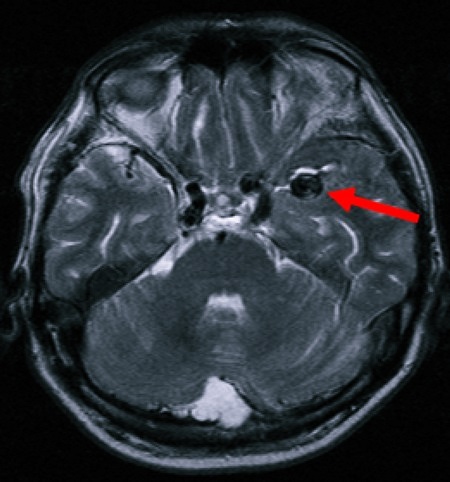

Что может показать МРТ? Данная диагностика выявляет наличие:

- Опухолей в головном мозге. Они могут быть доброкачественными, злокачественными. Методика помогает не только найти опухолевое образование, но и следить за его ростом, прогрессом проводимого лечения или процессом выздоровления пациента после перенесенного оперативного вмешательства.

- Ишемических инсультов и инфарктов головного мозга. Снимок позволяет определить зону ишемического поражения, стадию его развития, образование отека, плотность пораженных тканей, наличие некроза в мозговой ткани.

- аномалий в сосудах головного мозга. В данную категорию входит развитие аневризмов, тромбозов;